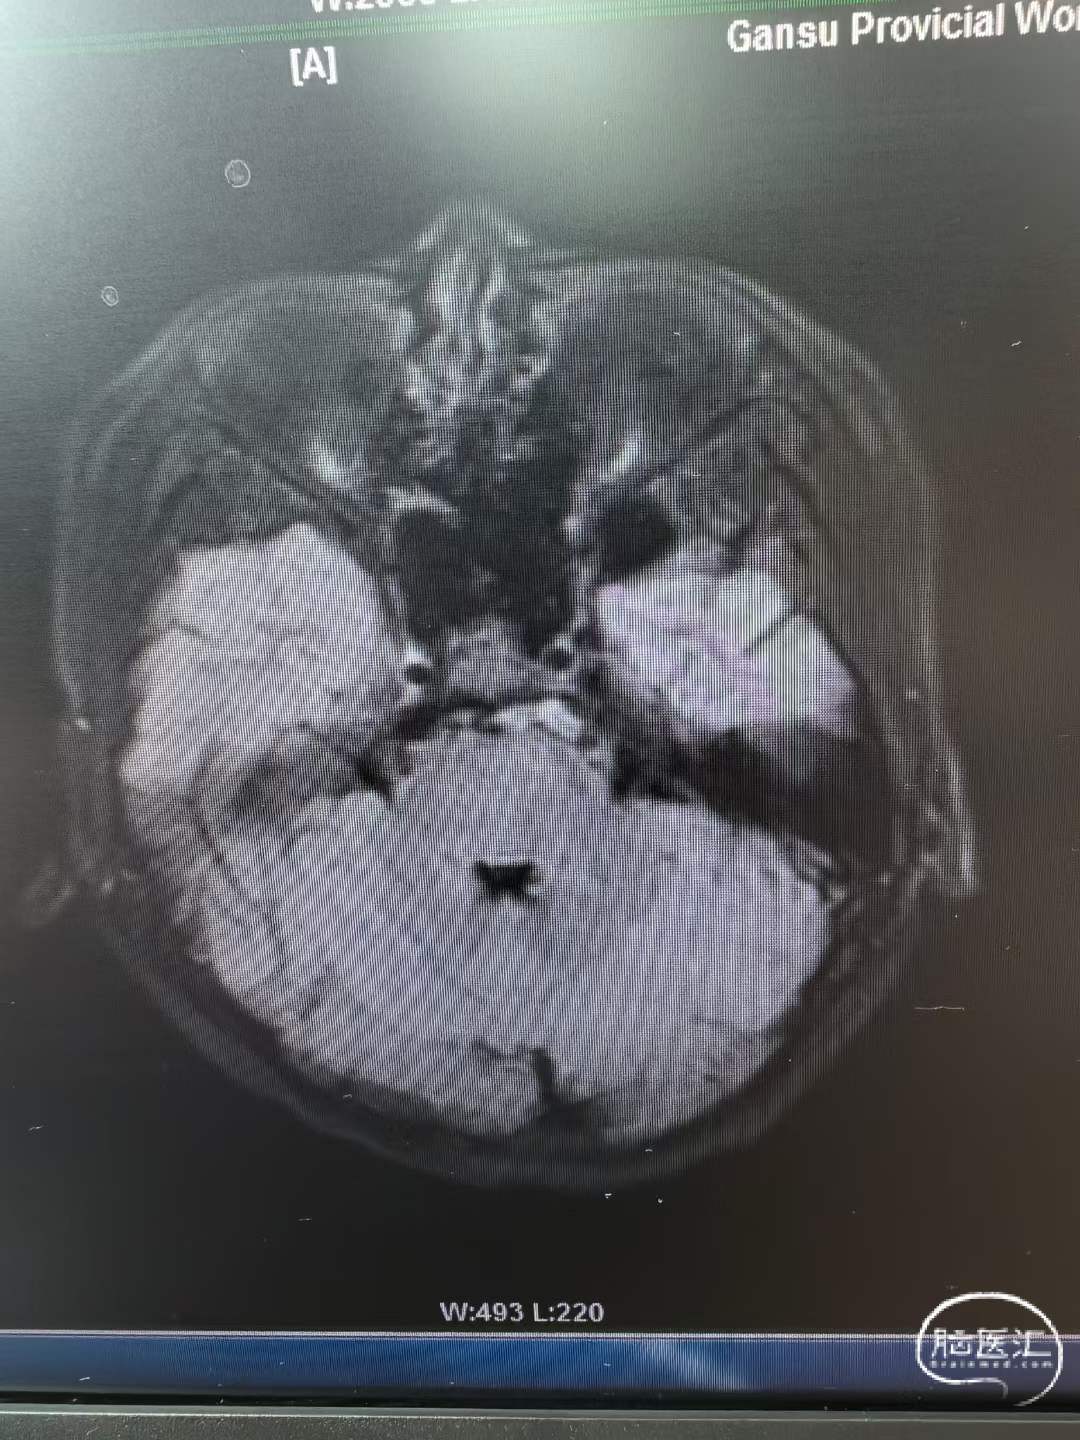

13岁的患儿,头痛2天,肢体无力伴意识障碍进行性加重1天,PICU张主任会诊后识别并怀疑急性脑血管病,转诊至我院,绿色通道评估后明确为基底动脉闭塞,患儿呈去脑干强直。

术后检查

基底动脉完全再通,期待随访。